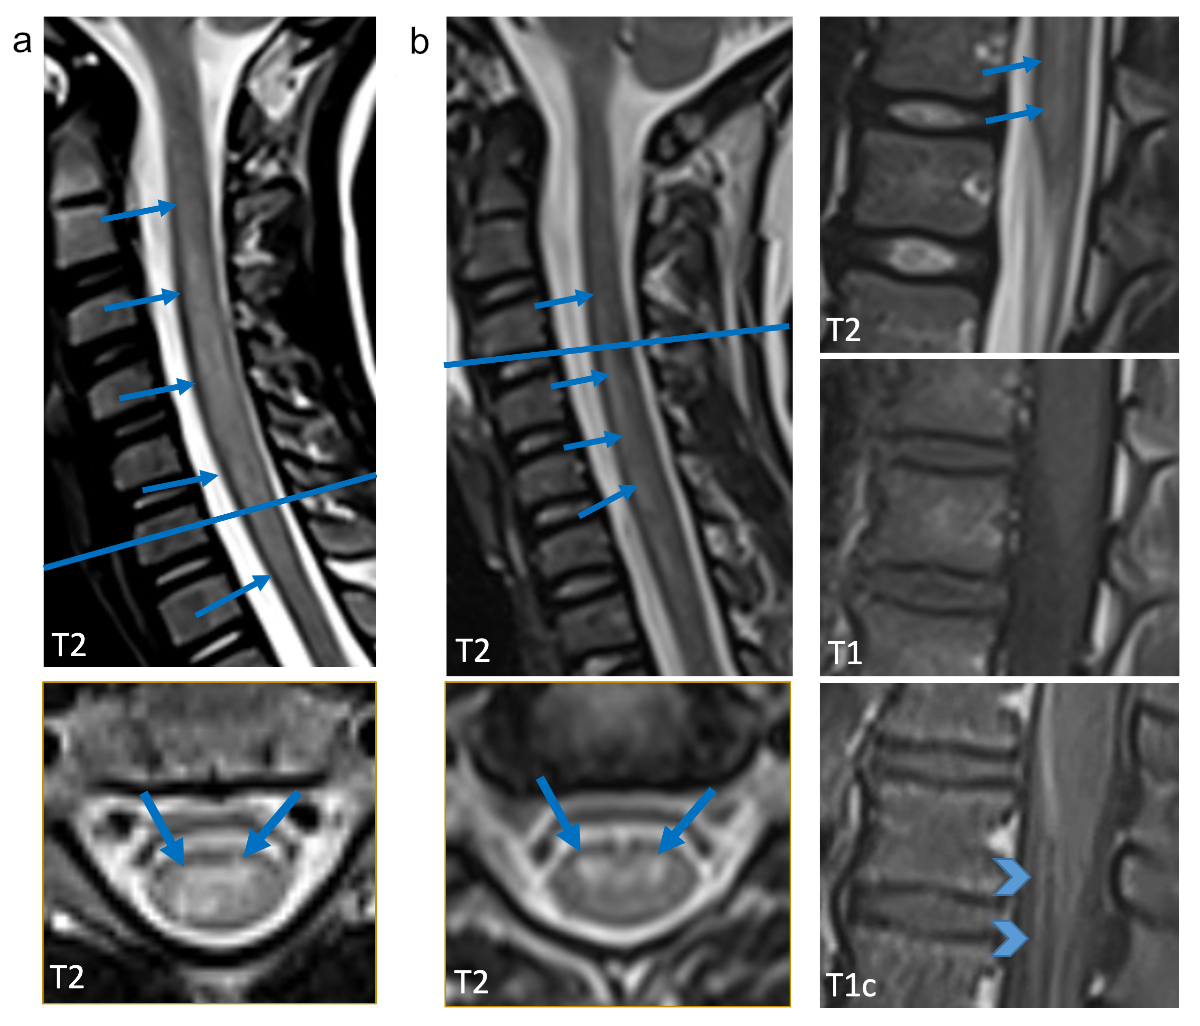

Patient 1 was a 9-year-old, previously healthy, male child with his immunisations up to date including the vaccines against poliomyelitis and tick-borne encephalitis. He came down with low-grade fever, rhinorrhoea and a sore throat in early November 2021. No other family member was ill, but he mentioned a similar illness among some of his classmates. Two days later he noticed complete inability to move his right arm and complained of orthostatic dizziness. On admission to the hospital, he was fully alert. His body temperature was 38.0°C. Heart rate, respiratory rate and transcutaneous O2 saturation were 92–145 bpm, 28/minute and 90–92%, respectively. General physical examination revealed mild pharyngeal redness, productive cough and mild jugular retractions, but was otherwise normal. Neurologically, he showed a near total flaccid palsy of his right arm with no ability to execute visible movements in his right shoulder and upper arm (muscle strength M0–1 on a conventional five-point scale [18]) and with limited function in his right hand and wrist (M2–3). There was no neck stiffness, no sensory impairment and no bladder dysfunction. Magnetic resonance imaging (MRI) revealed a contiguous T2-hyperintense lesion predominantly within the grey matter of the spinal cord reaching from the craniocervical junction to thoracic vertebra 1, indicative of myelitis (fig. 1, panel a).

Figure 1 Representative sagittal and axial T2w images are shown (a: patient 1, 9.3-year-old old boy; b: patient 2, 7.1-year-old girl) as well as T1w images with and without contrast agent (b). Cervical myelitis with increased T2 signal is present in both children (arrows), in the boy only in the cervical spinal cord (a), in the girl additionally in the lumbar spinal cord (b). On the axial slice predominant involvement of the grey matter is evident (arrows point to anterior horns). In b (second column) sagittal T1w images show enhancement of the cauda equina and anterior nerve root enhancement (arrow heads).Representative sagittal and axial T2w images are shown (a: patient 1, 9.3-year-old old boy; b: patient 2, 7.1-year-old girl) as well as T1w images with and without contrast agent (b). Cervical myelitis with increased T2 signal is present in both children (arrows), in the boy only in the cervical spinal cord (a), in the girl additionally in the lumbar spinal cord (b). On the axial slice predominant involvement of the grey matter is evident (arrows point to anterior horns). In b (second column) sagittal T1w images show enhancement of the cauda equina and anterior nerve root enhancement (arrow heads).

Patient 2 was a 7-year-old, previously healthy girl, whose illness started with fever above 39.0°C, rhinorrhoea and cough. No other family members had similar symptoms. Five days later and after the fever had subsided, her parents noted an abnormal gait, weakness of her left arm and speech difficulties. On admission, her temperature was 36.9°C. Heart rate, respiratory rate and transcutaneous O2 saturation were 102 bpm, 29/minute and 100%, respectively. Her general physical examination was normal. Neurologically, she showed bilateral paralytic disease. Assessment of muscle weakness revealed a patchy distribution with marked weakness in her left shoulder (M3) and mild weakness in her legs (M4, right proximal and left distal leg). There was no neck stiffness, no sensory impairment and no bladder dysfunction. MR1 revealed multilevel T2-hyperintense myelitis, affecting the grey matter of the spinal cord with contrast enhancement in the anterior horns of the grey matter. Additionally, there was leptomeningeal enhancement (fig. 1, panel B). Her laboratory data are listed in table 1. Microbiological tests were negative for enterovirus by PCR from both CSF and stool, but enterovirus PCR was positive in a nasopharyngeal swab. Both partial sequencing of the enteroviral VP4/VP2 region [19] and shotgun metatranscriptomic sequencing were unsuccessful in identifying EV-D68 or another enterovirus type molecularly. Her treatment consisted of intravenous high-dose methylprednisolone, followed by intravenous immunoglobulin (table 1). Her gait abnormality and speech disturbance disappeared within several days, but her left shoulder weakness persisted for several weeks. On her last follow-up visit 6 months after the onset of her illness, she had completely recovered.

The clinical manifestations in our two patients were prototypical for EV-D68-associated acute flaccid myelitis. They consisted of a febrile respiratory prodrome, followed by rapid-onset asymmetric motor weakness, moderate CSF pleocytosis and T2-hyperintense, longitudinally extensive spinal cord grey matter disease on MRI. Major differential diagnoses, such as Guillain-Barré syndrome, demyelinating disease, other infectious causes or spinal stroke were ruled out using appropriate laboratory (table 1) and neuroimaging studies (fig. 1) and by the subsequent clinical course. Although the differentiation between inflammation and stroke by MRI may be difficult, CSF pleocytosis in both cases clearly established an inflammatory process.